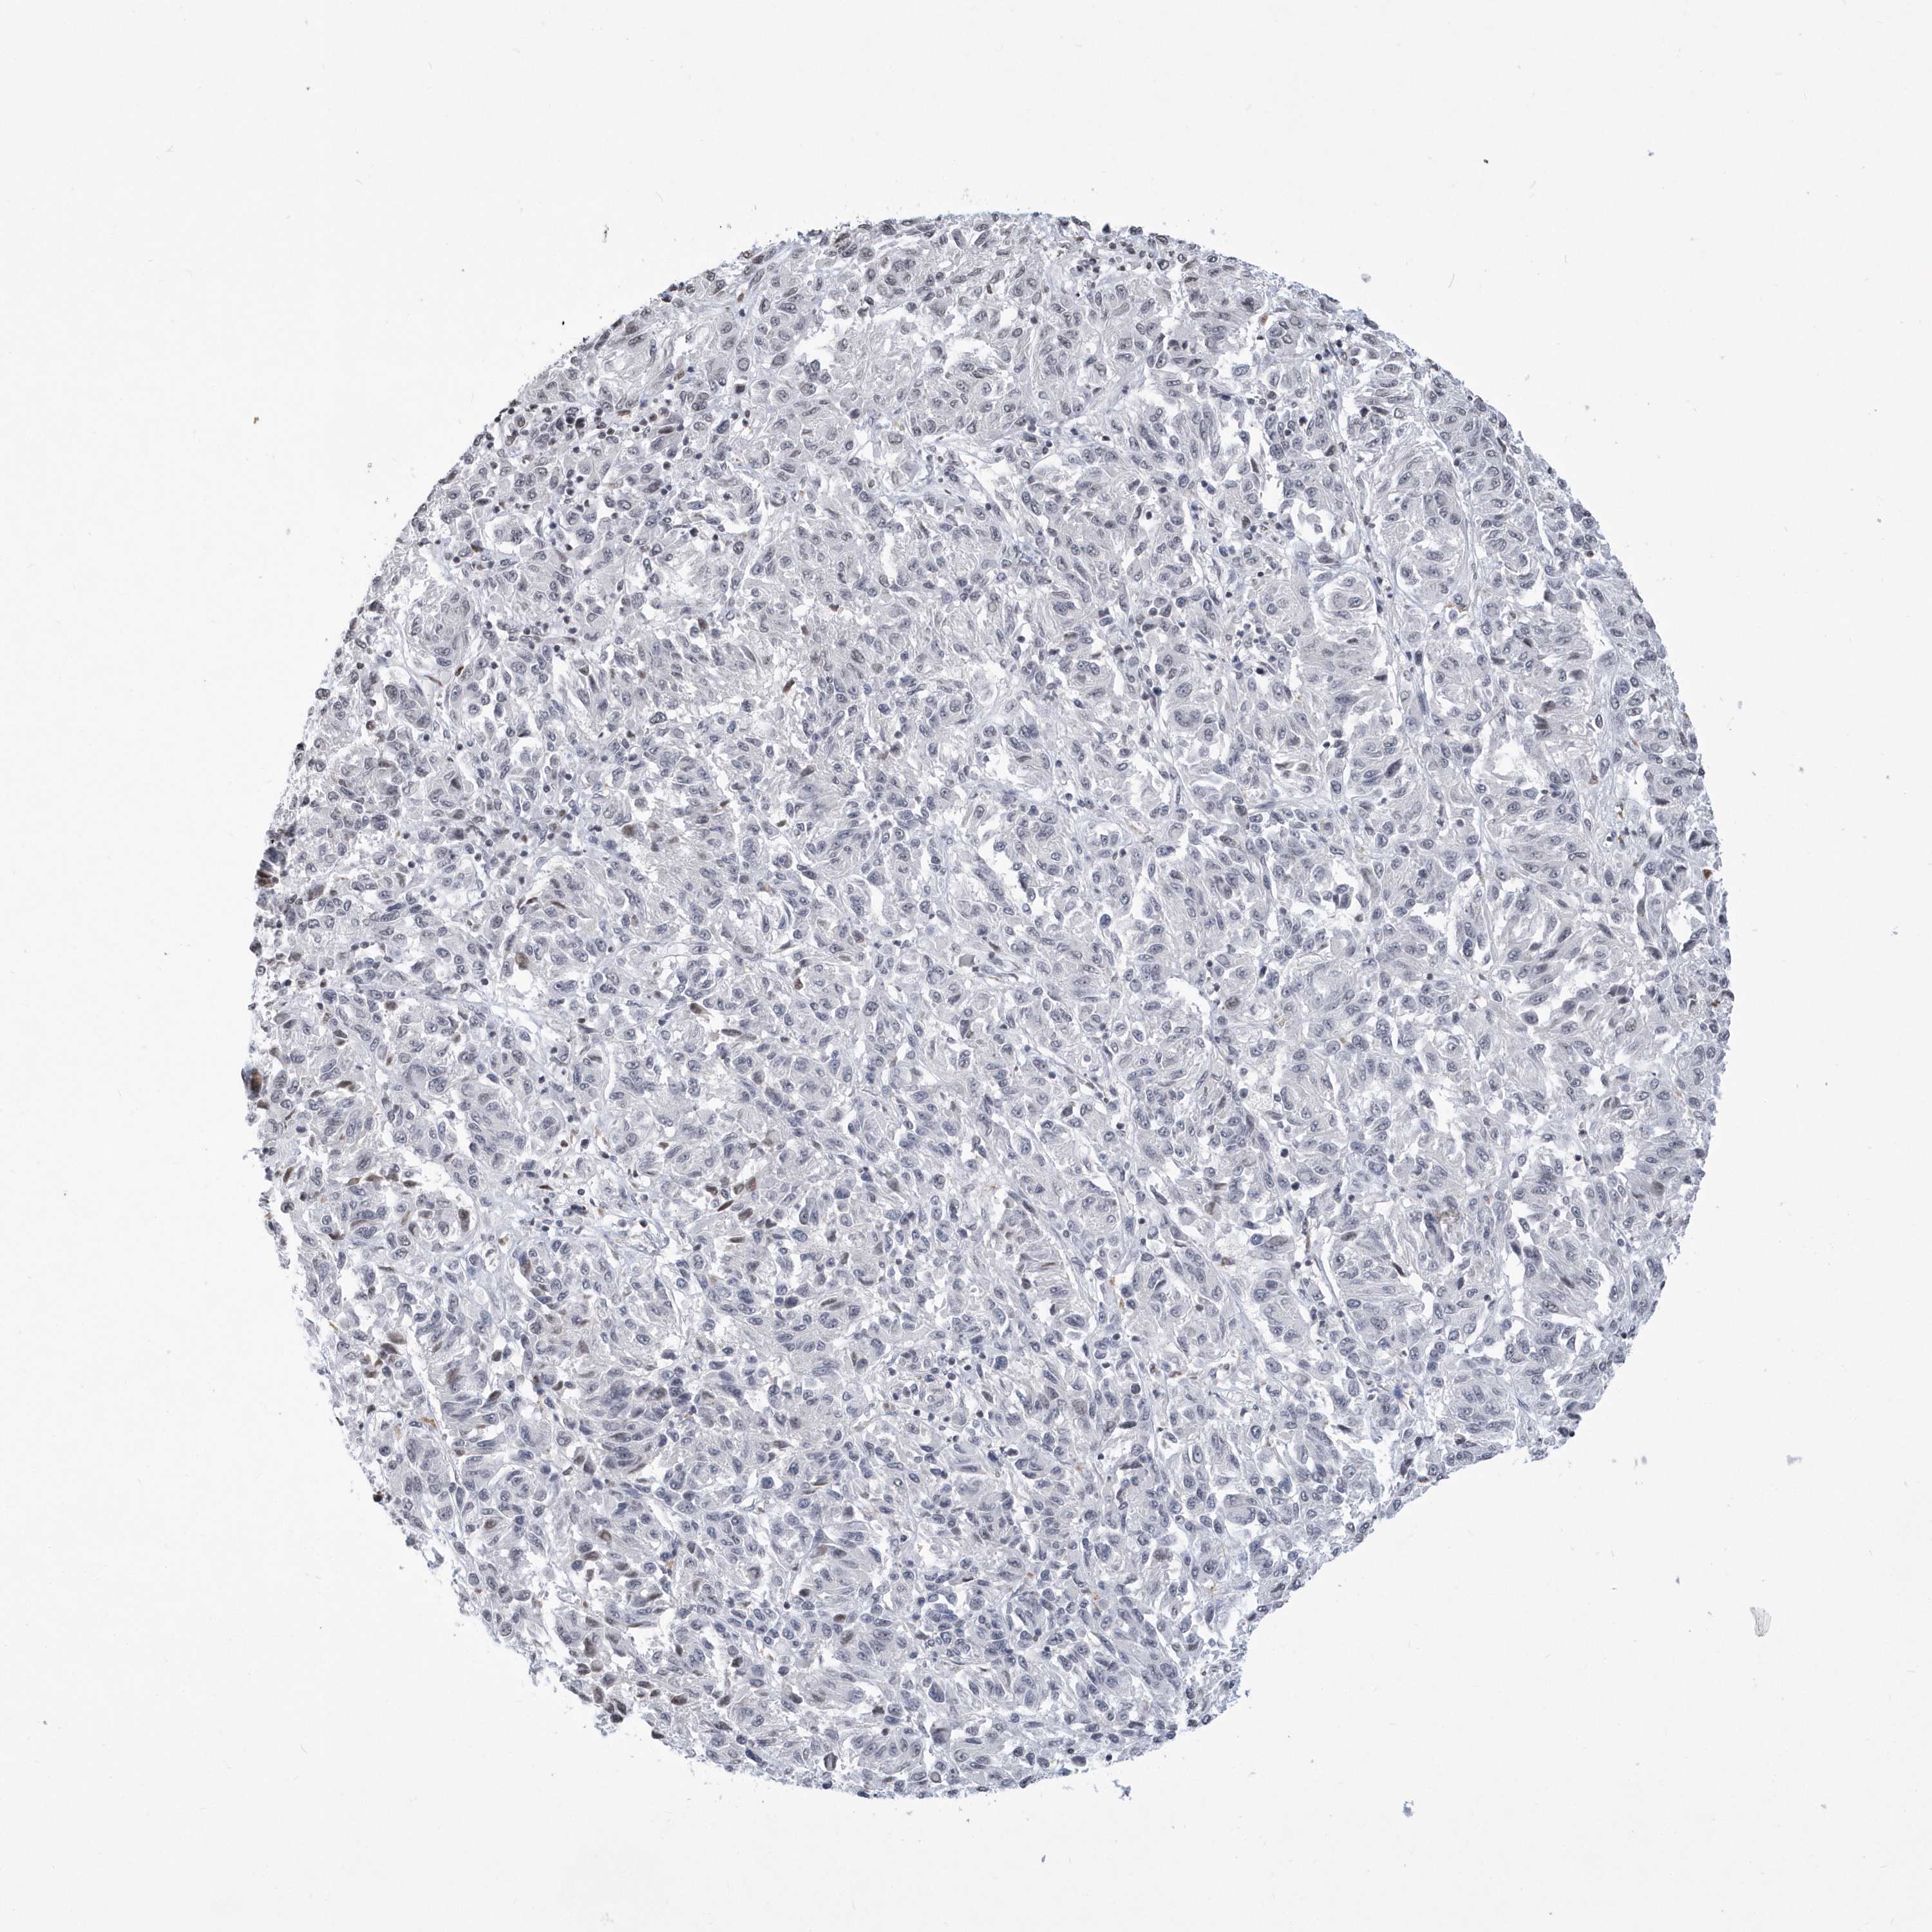

MELANOMA - Protein expressioni

A mouse-over function shows sample information and annotation data. Click on an image to view it in a full screen mode. Samples can be filtered based on level of antibody staining by selecting one or several of the following categories: high, medium, low and not detected. The assay and annotation is described here.

Antibody staining in the annotated cell types in the current human tissue is reported as not detected, low, medium, or high, based on conventional immunohistochemistry profiling in selected tissues. This score is based on the combination of the staining intensity and fraction of stained cells.

Each image is clickable and will lead to virtual microscopy that enables deeper exploration of all samples and also displays staining intensity scores, fraction scores and subcellular localization as well as patient and tissue information for each sample.

Antibody HPA036823

Antibody HPA036824

Antibody HPA061412

Malignant melanoma, NOS

Malignant melanoma, Metastatic site